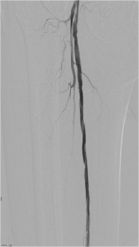

溶栓治疗后,后续又择期引入球囊导管,分别在左侧髂动脉、股浅动脉多处狭窄段进行球囊扩张,扩张后造影见血管扩张良好,血流通畅。